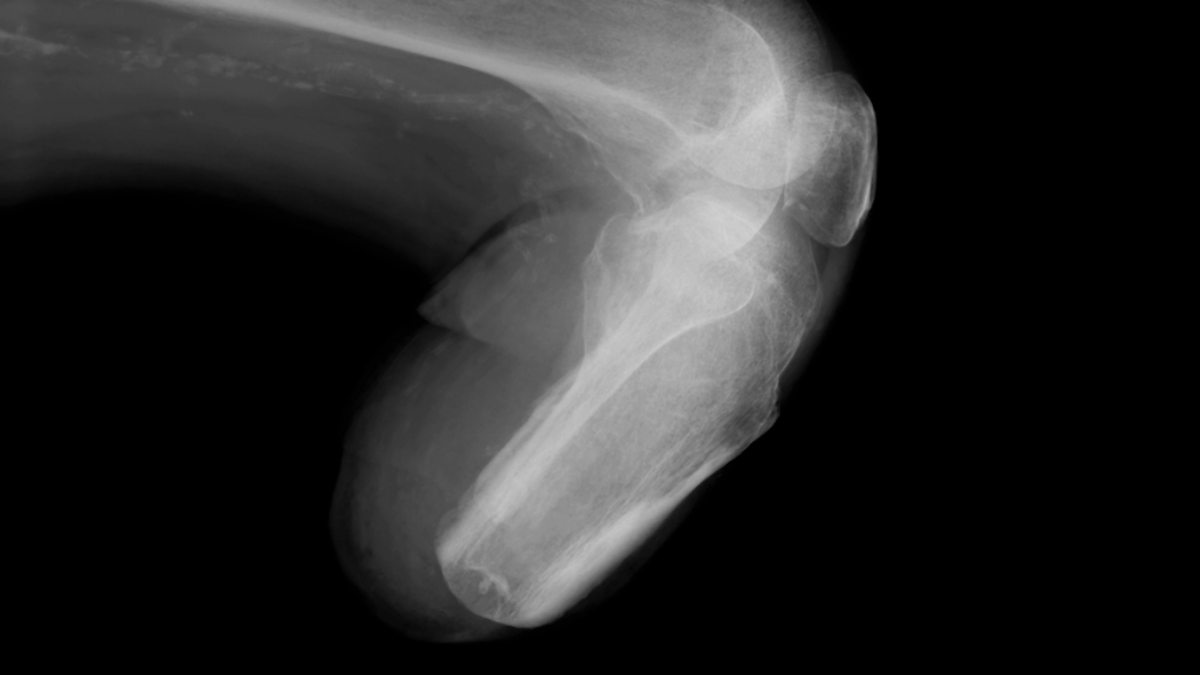

Культя рентген

Культя рентген 136 фотографий